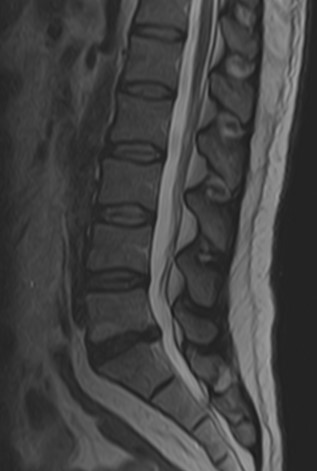

Lomber MRG

incelemesinde L5-S1 seviyesinde santral bir bulging görülmektedir. Sağ

S1 köküne dokunacak şekilde anulus fibrozusta küçük bir açıklık

ve ufak bir ekstrüde fragman varlığından şüphe edilebilse bile, kesin

söylenemez. Aynı seviyede disk içi hipointens ve komşu L5 vertebrası

alt endplate'i ön kısmında dejeneratif sinyal değişikliği görülmektedir

(dejeneratif disk hastalığı). Lomber lordoz korunmuştur. Diğer

disk seviyeleri, faset eklemler ve paravertebral kaslarda belirgin bir

sorun saptanmamıştır.